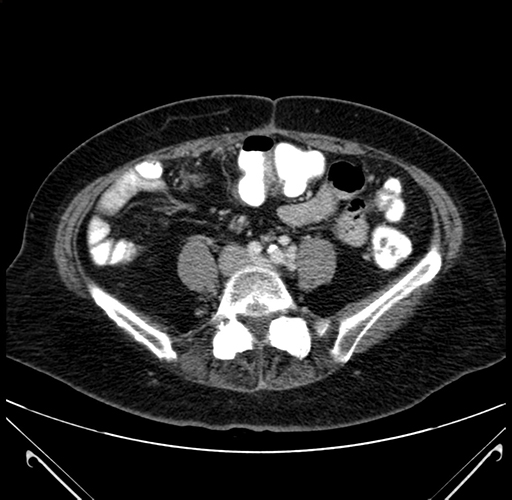

Pre-Chemo: Axial Venous

Axial Venous